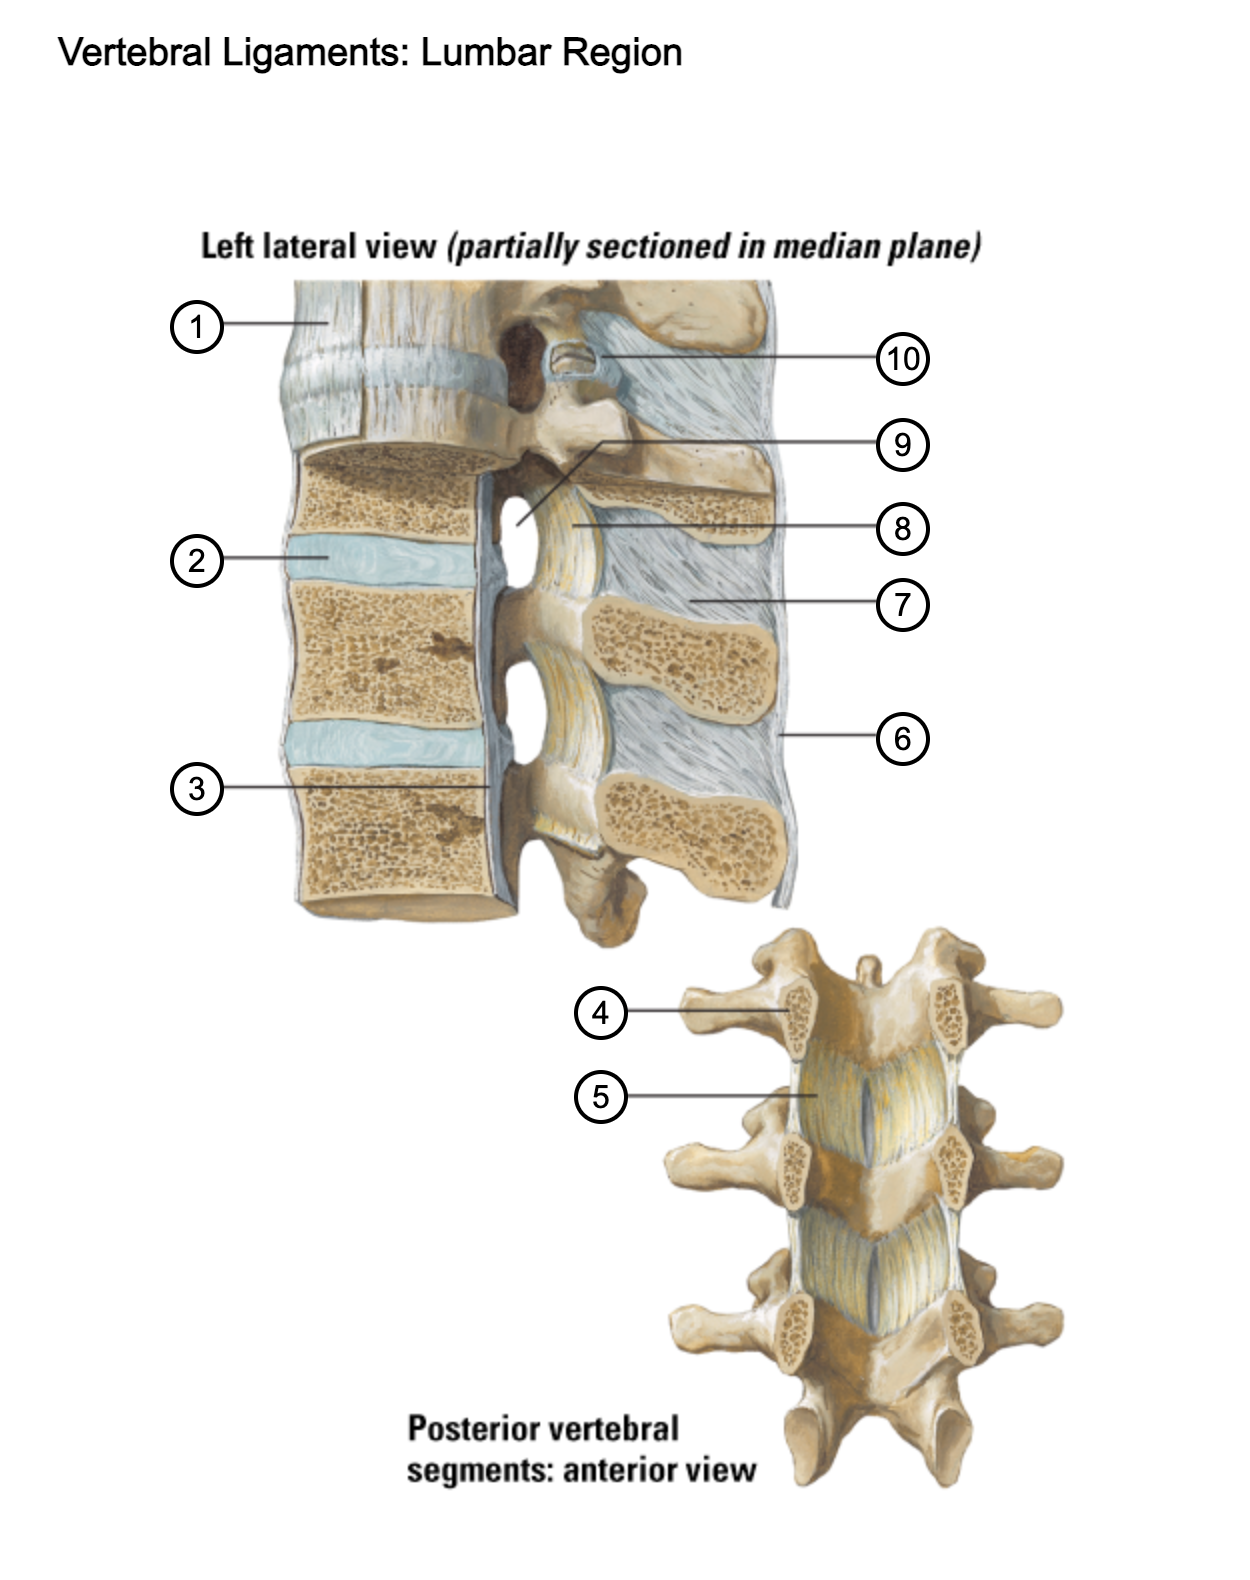

1

anterior longitudinal ligament

2

intervertebral disc

3

posterior longitudinal ligament

4

pedicle (cut surface)

5

ligamentum flavum

6

supraspinous ligament

7

interspinous ligament

8

ligamentum flavum

9

intervertebral foramen

10

capsule of zygapophysial join (partially opened)